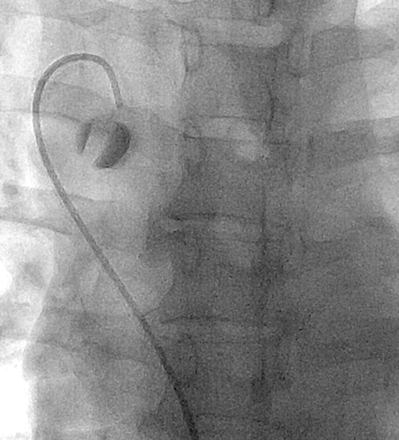

We therefore decided to investigate the CCSVI hypothesis by use of venography, which is considered to be the reference standard24 in evaluation of the venous system. The results of our study show significant discrepancies from those reported by Zamboni et al in terms of stenosis of the ILP (34% in our experience versus 9% of Zamboni et al4) and of the AV (20.5% versus 71%). Regarding the latter, the difference may be due to the fact that despite the evidence of what is defined by Zamboni et al as a “membranous obstruction at the junction of the AV with the superior vena cava” present in all patients (Fig 5), such finding never correlated with a reduced venous outflow or a significant abnormality in terms of intravenous pressure. Furthermore, these so-called “obstructions” were never associated with rachidian collaterals. In fact, AV arch valves have been reported to be common and should not necessarily be interpreted as pathologic findings.25

Selective catheterization of the azygos vein in a 45-year-old patient affected by relapsing-remitting MS. At the confluence of the azygos vein after administration of contrast medium, a valve is evident.